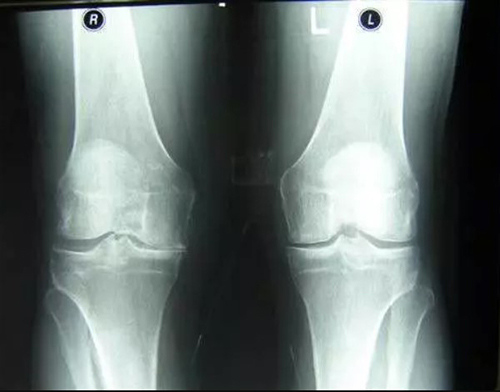

- แคลเซียมเกาะกระดูก (Osteophytes) คือตัวการของโรคข้อและกระดูกกว่า 97% เช่น โรคข้ออักเสบ โรคข้อเสื่อม โรคกระดูกอ่อน โรคกระดูกพรุน โรคไขข้ออักเสบ โรคถุงน้ำในข้ออักเสบ และแม้แต่ซีสต์ของปมประสาท

เมื่อเกลือเหล่านี้เกาะอยู่บนพื้นผิวของข้อต่อ คราบเกลือเหล่านี้เหมือนกระดาษทรายที่ทำลายเนื้อเยื่อรอบโดยรอบ กระดูก และกระดูกอ่อน เมื่อผลึกโตขึ้น เกลือจะเริ่มทำลายเนื้อเยื่อของกล้ามเนื้อ เอ็น หลอดเลือด และเส้นเลือดฝอย ทำให้เกิดการอักเสบ ติดเชื้อ บวม ก่อให้เกิดการอักเสบและปวดอย่างรุนแรง